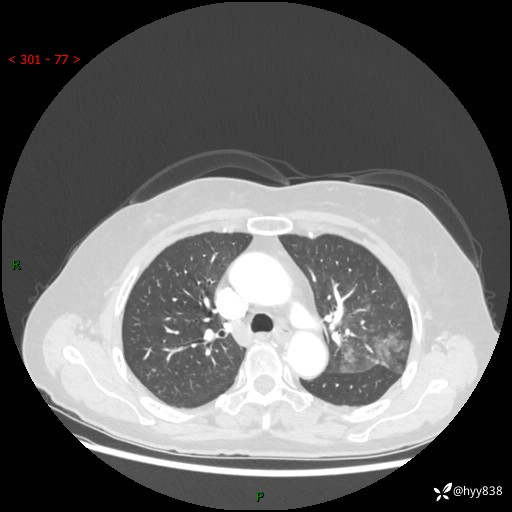

老年女性,偶然发现肺结节10天。结节不大,空洞不小,还牵拉胸膜---结果公布~

现病史:患者10余天前因“左侧鼻塞伴鼻腔异味2月”就诊于我院耳鼻喉科,查胸部CT示:左上肺结节影,建议复查。患者偶有咳嗽、咳痰,多咳白痰,无畏寒、发热,无胸痛、呼吸困难等,现为进一步明确肺结节性质,就诊于我科门诊。现以“孤立性肺结节”收住我科。 起病来,患者精神、食欲、睡眠尚可,体力、体重无明显变化。

胸部CT(2024.7.16)